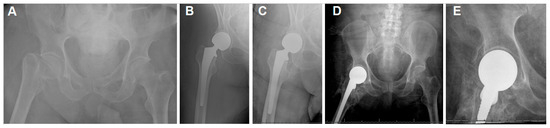

| Case | Age | CP Type | Implant Type | Complications | Outcome |

|---|---|---|---|---|---|

| 1 | 71 | Ataxic | Cemented bipolar | HO grade 4 | |

| 2 | 55 | Quadriparitic | Cemented bipolar | Dislocation and early revision due to stem loosening. Recurrent dislocation managed with closed reduction and bracing. | Ho grade 3 |

| 3 | 68 | Ataxic | Cementless unipolar | HO grade 4 | |

| 4 | 60 | Unidentified | Cemented bipolar | HO grade 2 | |

| 5 | 33 | Contralateral spastic hemiplegic | Cemented bipolar | HO grade 3 | |

| 6 | 47 | Ipsilateral spastic hemiplegic | Cementless bipolar | Acetabular protrusion, wheelchair bound | HO grade 4 |